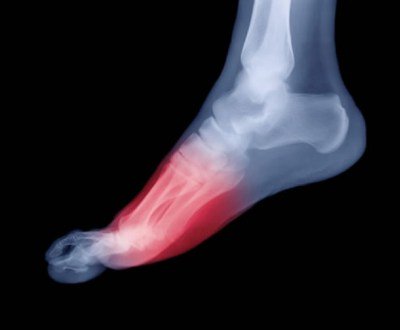

Подошвенный фасциит

Воспаление фасций стопы, появляющееся как результат чрезмерных нагрузок. Чаще всего беспокоит спортсменов, людей с чрезмерной массой тела и пациентов с прогрессирующей формой плоскостопия.

В запущенных формах переходит в пяточную шпору.

Симптомы Обнаружить болезнь можно по болям на внешней стороне стопы и сбоку, усиливающимся по утрам, при этом воспаляется подошва. Со временем появляется сильная хромота, которая при отсутствии лечения может превратиться в хроническую. Лечение При диагностировании подошвенного фасциита пациенту назначают стандартное лечение, включающее курс массажа, ношение специальной обуви, медикаментозные препараты, а также специальные упражнения, направленные на облегчение последствий нагрузок на стопу.

- Подошвенный фасциит

Подошвенная фасция – это полоска соединительной ткани, которая соединяет плюсневые и пяточную кости, образуя свод стопы. Она поддерживает стопу и служит амортизатором при ходьбе и беге. Воспаление подошвенной фасции называется подошвенный фасциит. Его причиной чаще всего становится бег по твердой поверхности, обувь с жесткой подошвой, а также интенсивный бег в гору.